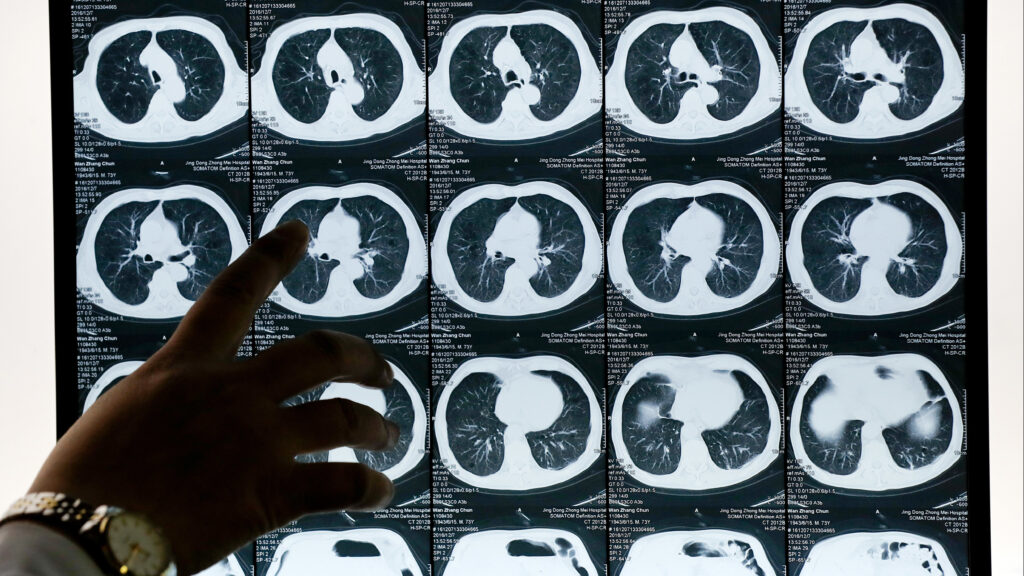

the Mirati drug, called adagrasib, shrank tumors in 43% of patients with advanced lung cancer

With new data on its KRAS-blocking lung cancer drug, Mirati expects to take on a rival Amgen treatment

s Mirati Therapeutics waits for the Food and Drug Administration to complete a review of its KRAS-targeting lung cancer drug later this year, final results from a clinical trial reported...